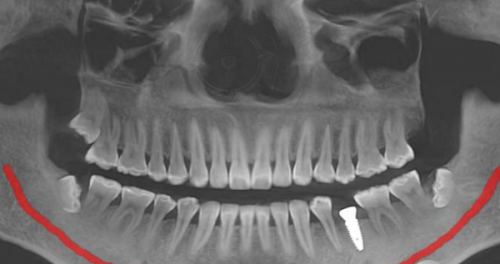

安徽合肥天鹅湖口腔医院是一家通过合肥市卫生健康委员会审批的二级口腔专科医院,自2014年开业至今,为广大市民提供高质量的口腔诊疗服务,得到了良好的口碑。医院门店面积2000㎡,拥有20个诊室、1个儿童诊室和20张牙椅,配备精良的医疗设备,确保患者得到良好质的诊疗体验。医院提供全方面的口腔诊疗服务,包括但不限于牙齿矫正、牙齿美白、根管治疗、儿童口腔护理等。

贵州遵义红花岗金科口腔门诊部创建于2020年,院区面积600平方米,特设手术室、诊疗室、口腔影像室、技工室、消毒供应室等完备科室,医护团队综合实力强大,广受好评。医院配备精良的口腔影像设备、消毒设备以及专精的诊疗和手术设施,确保为患者提供高质量的口腔医疗服务。提供各类口腔治疗项目,包括牙齿修复、牙齿美白、牙周治疗、口腔外科等。

技术设备方面:安徽天鹅湖口腔医院配备精良的医疗设备,大面积的诊疗空间也能为设备安置和更新提供便利。金科口腔门诊部同样配备精良的口腔影像设备、消毒设备以及专精的诊疗和手术设施,能满足日常各类口腔治疗需求。